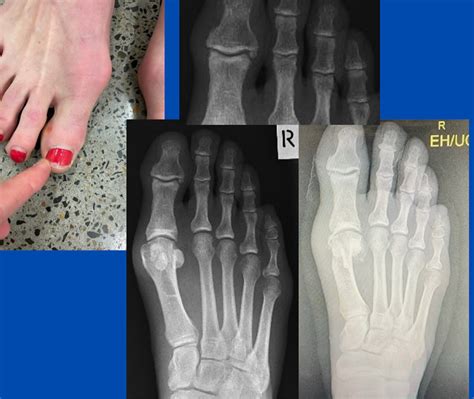

• Surgical Planning: If surgery is required, the X-ray acts as a blueprint to determine which type of osteotomy or fusion is necessary.

If the Bunion X Ray indicates a severe deformity, or if conservative treatments fail to provide relief, surgical correction may be proposed. Surgery aims to realign the metatarsal bone, remove the bony prominence, and stabilize the joint. Because the bone structure is unique to every patient, the X-ray is the most important tool for a surgeon to visualize the exact alignment needed to restore a pain-free gait.

• bunion x ray vs normal

• bunion correction xray